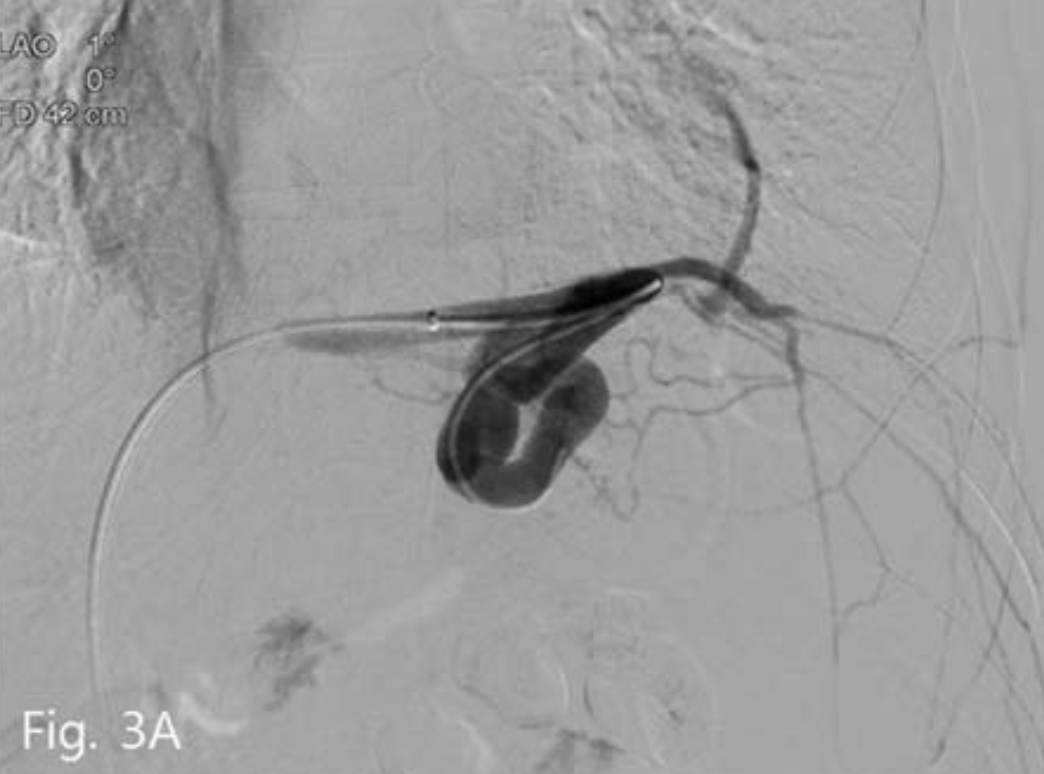

8-Fr sheath를 5-Fr catheter와 wire의 support 하에 gastrocaval shunt내로 진입시킨 후 wire를 남기고 catheter를 제거하였다. 그 후 sheath를 통해

16mm vascular plug II(Amplatzer Vascular plug; AGA Medical, Golden Valley, Minn)를 삽입하였다. 그 후 wire를 따라 5-Fr catheter를 vascular plug를 지나 위치시키고 정맥조영술을 시행하였으며 주 유출정맥인 위대정맥단락은 막혔으나 대신 심장막정맥을 통한 곁가지 정맥배출이 좀 더 명확해졌다(Fig. 3B), 그래서 4개의 microcoil(Vortex; Boston Scientific, Cork, Ireland)로 이를 색전하였다(Fig. 3C). 그 후 5-Fr catheter를 통해 gelatin sponges(Gelfoam:

B. Vascular plug placement (arrow) is performed in gastrocaval shunt Left inferior phrenic vein and pericardial vein (arrowhead) is more prominently visualized.

C. Left inferior phrenic vein is embolized with microcoil (arrow). And then gastric varices is completely filled with gelfoam mixture.